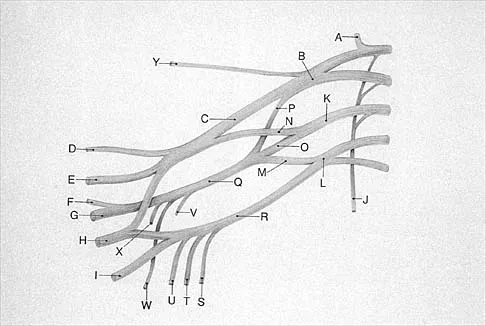

Question 47

What structure is marked Q in the diagram of the brachial plexus shown in Figure 22?

Explanation